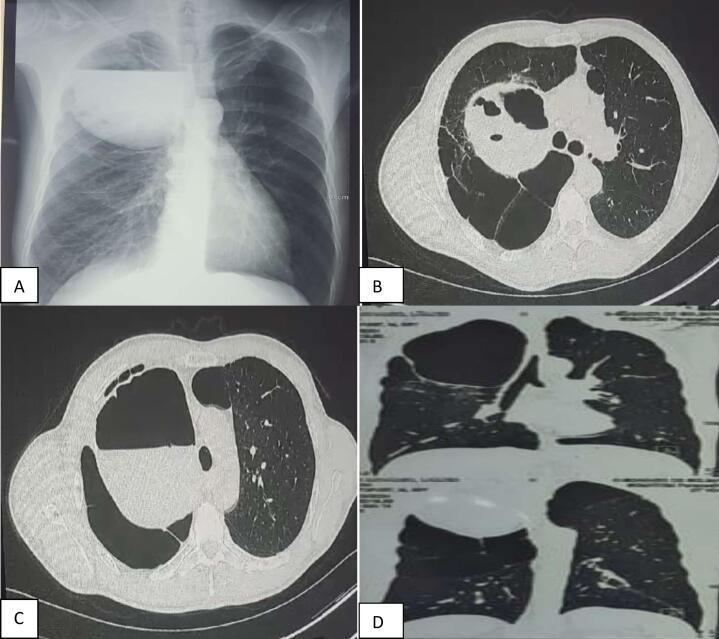

CASE PRESENTATION

We present a case series of seven male patients with an average age of 46 years, all diagnosed with infected emphysema bullae. The predominant clinical symptom was chest pain, often accompanied by fever and chills. Chest X-rays revealed hyperclarity occupying more than two-thirds of the pulmonary field in all patients. A follow-up CT scan confirmed the presence of large bullous emphysema. All patients received antibiotics for one to two weeks before surgery.

我们报告了一组7例男性患者的病例系列,平均年龄46岁,均被诊断为感染性肺气肿大疱。主要临床症状为胸痛,常伴有发热和寒战。胸部X线显示所有患者肺部透亮度增加,占肺野的三分之二以上。随访CT扫描证实存在大疱性肺气肿。所有患者在手术前接受了一到两周的抗生素治疗。